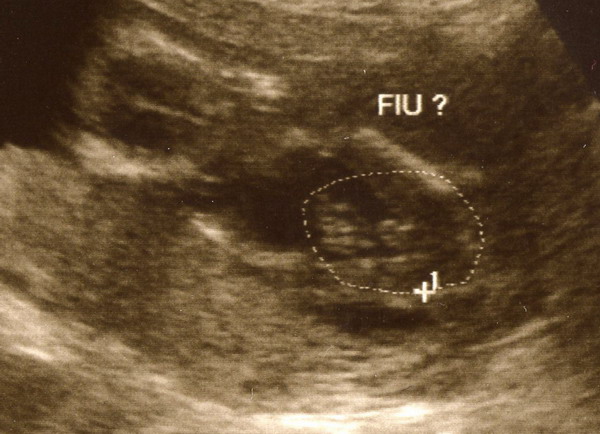

Minyu: beírnál nekem következő vizsgálatnak 04.22-t? 1re megyek genetikai UH-ra